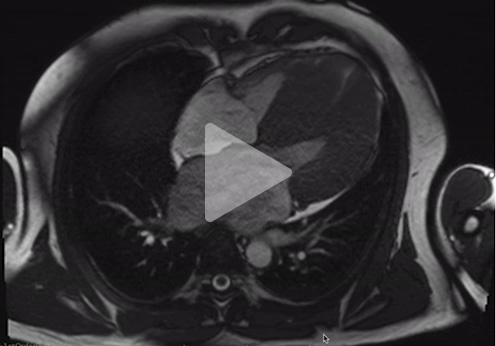

Voici son IRM

Vidéo 7 : IRM myocardique, 4 cavités, séquence ciné

Compte rendu de l'IRM myocardique

Conclusion :

- FEVG normale à 69%. Dilatation importante du VG. HVG très asymétrique jusqu'à 33mm

- FEVD normale à 73%. Pas de dilatation du VD. HVD débutante

- IM de haute grade (FR : 56%). Importante dilatation de l'oreillette gauche

- Fibrose sévère notamment en antéro-septale tel que décrit. Pas de séquelle d'infarctus myocardique